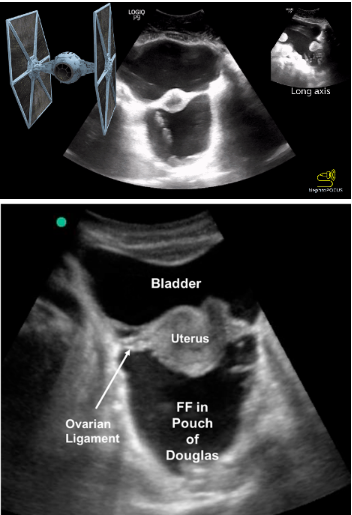

VOTW: In a pelvis, far far away

27 yoF presented to the ED with acute onset abdominal pain and distention. An ultrasound was performed that showed intraperitoneal fluid. Free fluid was identified at the liver tip and in the pouch of Douglas (video 1).

As a reminder, the pouch of Douglas is the potential space between the uterus and rectum (seen in the suprapubic view).

Video 1 shows something called the “TIE fighter sign,” where large amounts of free fluid fill the pouch of Douglas, posterior to the uterus. The uterus and ovarian ligaments are suspended between the pouch of Douglas and the bladder. This sonographic sign is based on the fact that the appearance of the uterus and ovarian ligaments looks like the “Twin Ion Engine” fighter from the Star Wars movies (Image 1).

While the free fluid was initially presumed to be from a ruptured ovarian cyst, the patient remains admitted to workup this ascites of unknown etiology